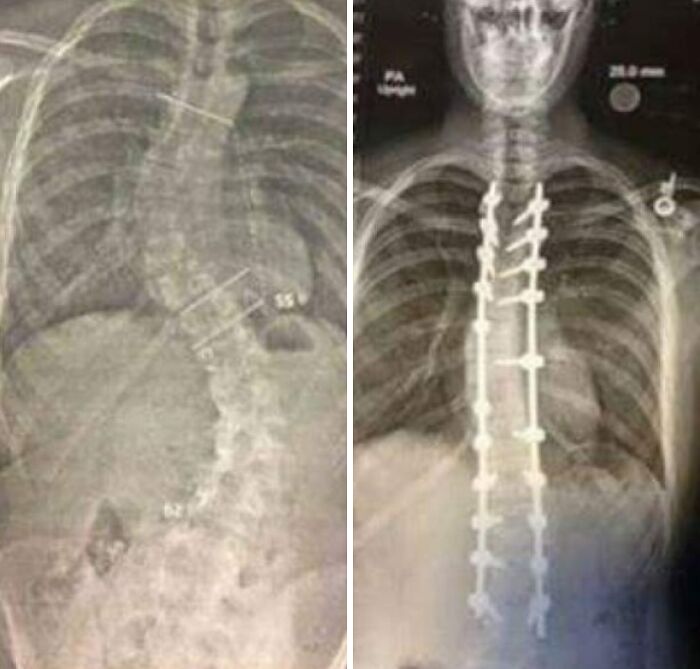

#14 These Are X-Rays Taken Before And After The Surgery

It has been 4 years to the day since I had my scoliosis surgery. The surgery itself took 14 hours. Surgeons drilled metal straightening bars into my spine.

Image credits: River_Atkinson